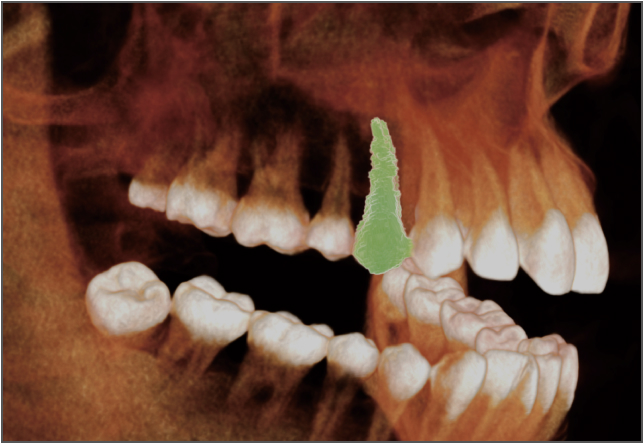

• lamtau 单颗牙齿分割

单颗牙齿分割